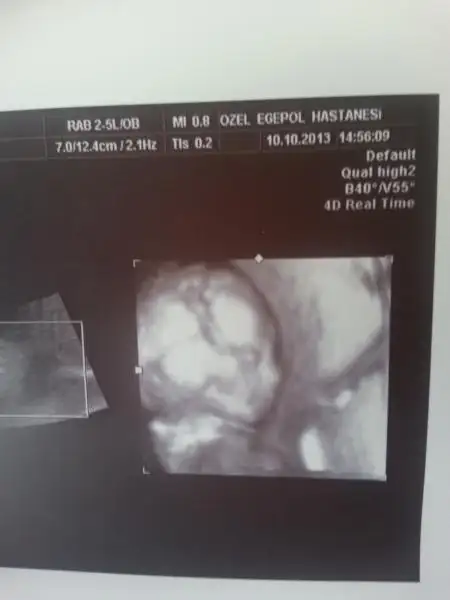

Gittik doktorcuğumuza. Gördük kızçemizi. Önce normal incelemeleri yaptı doktor..

Sonra gelelim en merak ettiğiniz yere dedi. Biz cinsiyeti bilmiyoruz sanıyo falan diye düşündük.

Meğersem yüzünden bahsediyormuş :1:

Açtı renkliyi gösterdi yüzünü ve bacaklarını. Babamıza benzicez sanırım. Anası gibi uzun yüzlü değil, yuvarlak yüzlü olcak galiba kızım :)

evet kızlar bugün ayrıntılı ultrasonum vardı herşey çok iyi normal haftasıyla yumlu bebeğim kollar bacaklar kalp damarlar mide böbrek vs iç organlar hepsini gördük maşşalah sizlerinde öle çıkar :)